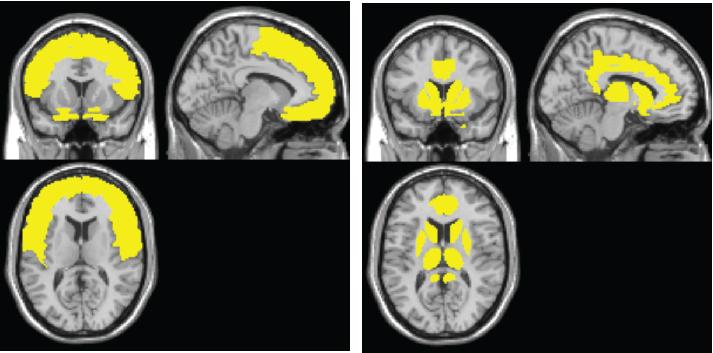

image: The MRI scan on the left reveals gray matter atrophy commonly seen in a person with HIV. On the right, the atrophy is associated with HAND, establishing a new profile for the disorder. view more

The model shows the sweep of atrophy that occurs as time passes from initial viral infection. It suggests that early on in HIV+ disease, the virus affects the frontal lobe, considered to be the essential hub of brain networks, responsible for such high-level tasks as attention and executive and cognitive functioning. By contrast, the injury to the caudate/striatum area, a subcortical region and part of the motor and reward system, becomes more prominent when individuals develop clinical HAND symptoms.

The researchers found that the frontal region (including anterior cingulate cortex, or ACC) is the most frequently affected brain region in HIV+ adults, whereas the neural injury to the caudate/striatum was consistently linked to neurocognitive impairment.

These results suggest a two-stage model of HAND in the context of brain atrophy, with a frontal/ACC stage that links to HIV disease and likely other comorbidities, such as substance abuse, and a caudate/striatum stage that links to neurocognitive impairment. "These two areas likely play different roles in HAND," Jiang says.